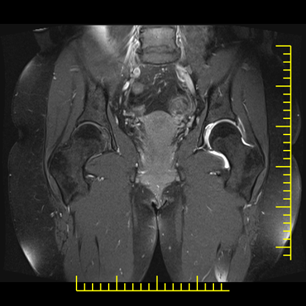

22. veljače 2026.Artrografija zglobova je specijalizirana dijagnostička metoda kojom se uz primjenu kontrastnog sredstva detaljno prikazuju strukture unutar zgloba – hrskavica, labrum, ligamenti, kapsula i tetive.

Artrografija kuka

MR artrografija kuka posebno je važna kod sumnje na oštećenje acetabularnog labruma i femoroacetabularni impingement (FAI).

Najčešće indikacije

- bol u preponi bez jasnog uzroka

- sportske ozljede kuka

- sumnja na labralnu leziju

- rana degenerativna oštećenja

- planiranje operativnog zahvata

Prednosti u odnosu na standardni MR

- bolja vizualizacija labruma

- jasnije definirane pukotine hrskavice

- preciznija procjena intraartikularnih lezija

Kod mlađih pacijenata s bolovima u kuku artrografija može otkriti rane promjene koje još nisu vidljive na klasičnoj magnetskoj rezonanciji.